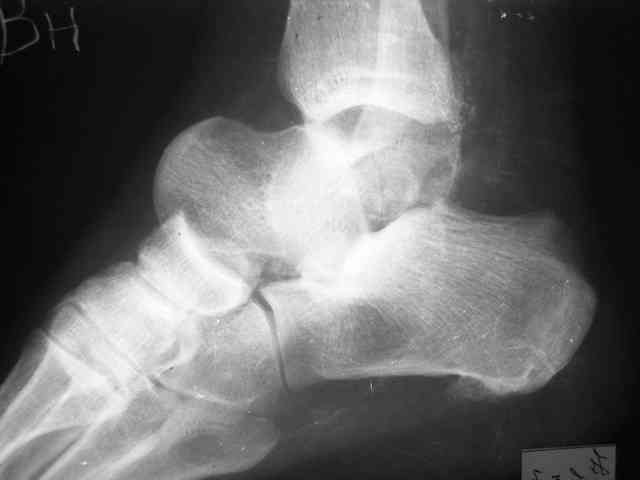

Уважаемый Александр! Как обещал представляю Р-граммы и операционные фото.

Ваши (лично ваши) рекомендации - астрагалэктомия-аппаратный пяточно-большеберцовый артродез с одновременным удлинением голени - правильно?

А удлинять голень в условиях плохих сосудов как? В смысле как потянутся склерозированные сосуды? Удлинять-то надо около 3 см.